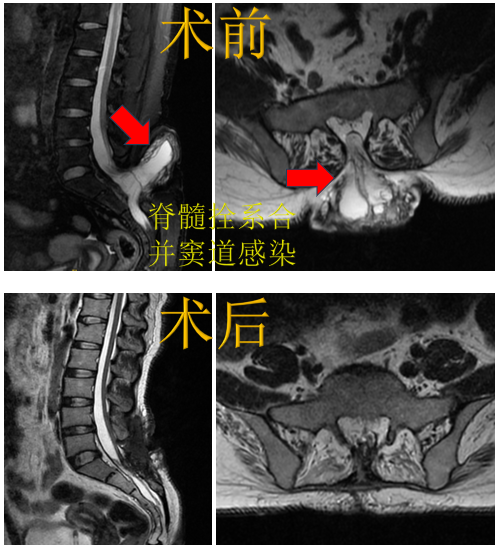

病例3.脊髓拴系合并窦道感染,行拴系松解+终丝切断+清创术。